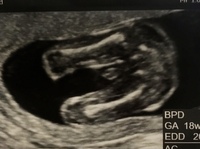

男の子のエコー写真 男の子のシンボルが見えやすいエコー写真を集めてみました! ぜひ参考にしてみてくださいね☆ 17週の男の子のエコー写真 左側がお尻、上下に足が見え、その間にシンボルが見えます。 19週の男の子のエコー写真17週0日(17w0d・男の子)|Ayako さん(32歳) エコー写真撮影時のエピソード: 戌の日の安産祈願に行った時に周りの妊婦さんがかなりお腹が大きかったのに、私はお腹がなかなか大きくならずに心配していましたが、エコーの赤ちゃんはきちんと大きくなっていて安心できました。性別判定のため17週で4Dエコーを受けてきました!17w6d時点 何故4Dエコーを受けようと思ったのか 安定期に入ってから性別が気になり出しました。辛かったつわりは絶賛継続中です。 ただ以前ほどではなく布団の中での生活からは抜け出せています。

17週のときのエコーです!これは男の子のシンボ 写真多数週数別女の子のエコーの見分け方! 妊娠17週目エコー写真・胎児の大きさ・胎動や性 17週 性別 男の子 エコー エコー写真の性別判断 妊娠17週目(17w0d~6d)のエコー写真とエピ男の子のエコー写真の 17週のエコーです。性別は男の子で確定でしょうか??? 早く分かれば名前決めたりしたいなあ どう思われますか?皆さんのエコーが見たいです 6月3日 お気に入り 妊娠17週目 性別 男の子 名前 エコー choco (3歳8ヶ月) コメント 6月 3男の子のエコー写真 男の子のシンボルが見えやすいエコー写真を集めてみました! ぜひ参考にしてみてくださいね☆ 17週の男の子のエコー写真 左側がお尻、上下に足が見え、その間にシンボルが見えます。